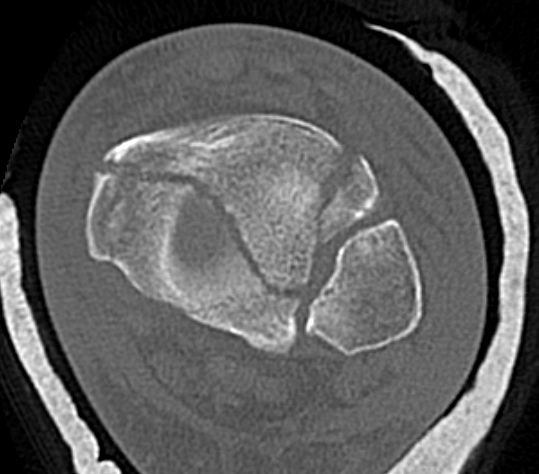

Commonly 3 fracture configurations

- medial malleolus

- posterolateral fragment / Volkmann

- anterolateral fragment / Chaput

Tibial plafond common fragmentsTibial plafond fragments